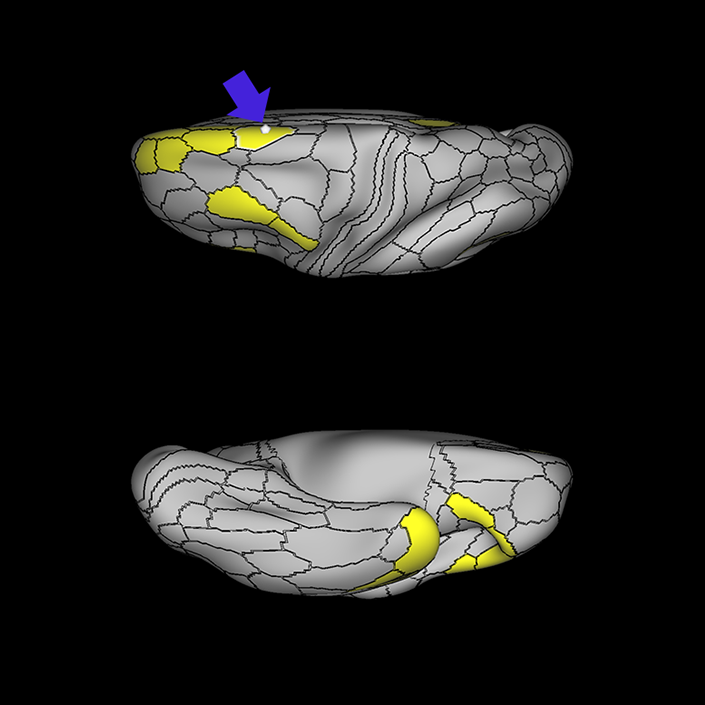

ᐅ SummaryArea 45: part of the inferior frontal gyrus of the lateral frontal lobe. In addition to its known association with Broca's area, is sometimes represented as part of Broca's complex ᐅ Where is it?Area 45 is the lateral surface of pars triangularis of the IFG. ᐅ What are its borders?Area 45 borders area 47L anteriorly and area 44 posteriorly. Its superior edge borders area p47r, IFSa, and IFSp. Its opercular surface is conveniently named FOP5 ᐅ What are its functional connections?Area 45 demonstrates functional connectivity to areas SFL, IFSp, 44, a47r, 47s, 47L, 9a, 9p, 9m, 8AV, and 8BL in the dorsolateral frontal lobe, area 8BM in the medial frontal lobe, area 55b in the premotor areas, areas FOP5, and PSL in the insula-opercular region, areas TGd, TGv, TE1a, STSva, STSdp and STSvp in the temporal lobe, area PGi in the inferior parietal lobe, and area 31pd in the medial parietal lobe. ᐅ What are its white matter connections?Area 45 is structurally connected to the arcuate/SLF and IFOF. However, arcuate/SLF connections are not consistent across individuals. Connections with the arcuate/SLF project posteriorly and wrap around the Sylvian fissure to the middle temporal gyrus to end at TE1p. There are also projections from the arcuate/SLF before it terminates to parcellations A4 and PBelt. IFOF connections travel from 45 through the extreme/external capsule and continue posteriorly through the temporal lobe to end at occipital lobe parcellations V1, V2, V3 and V4. Local short association bundles connect with 44 and FOP4. ᐅ What is known about its function?Area 45, in addition to its known association with Broca's area, is sometimes represented as part of "Broca's complex", including Brodmann Areas 45, 46, 47 and the mesial supplementary motor area of 6, which contribute to a frontal-subcortical circuit. |

A: lateral-medial

B: anterior-posterior

C: superior-inferior

DTI image |